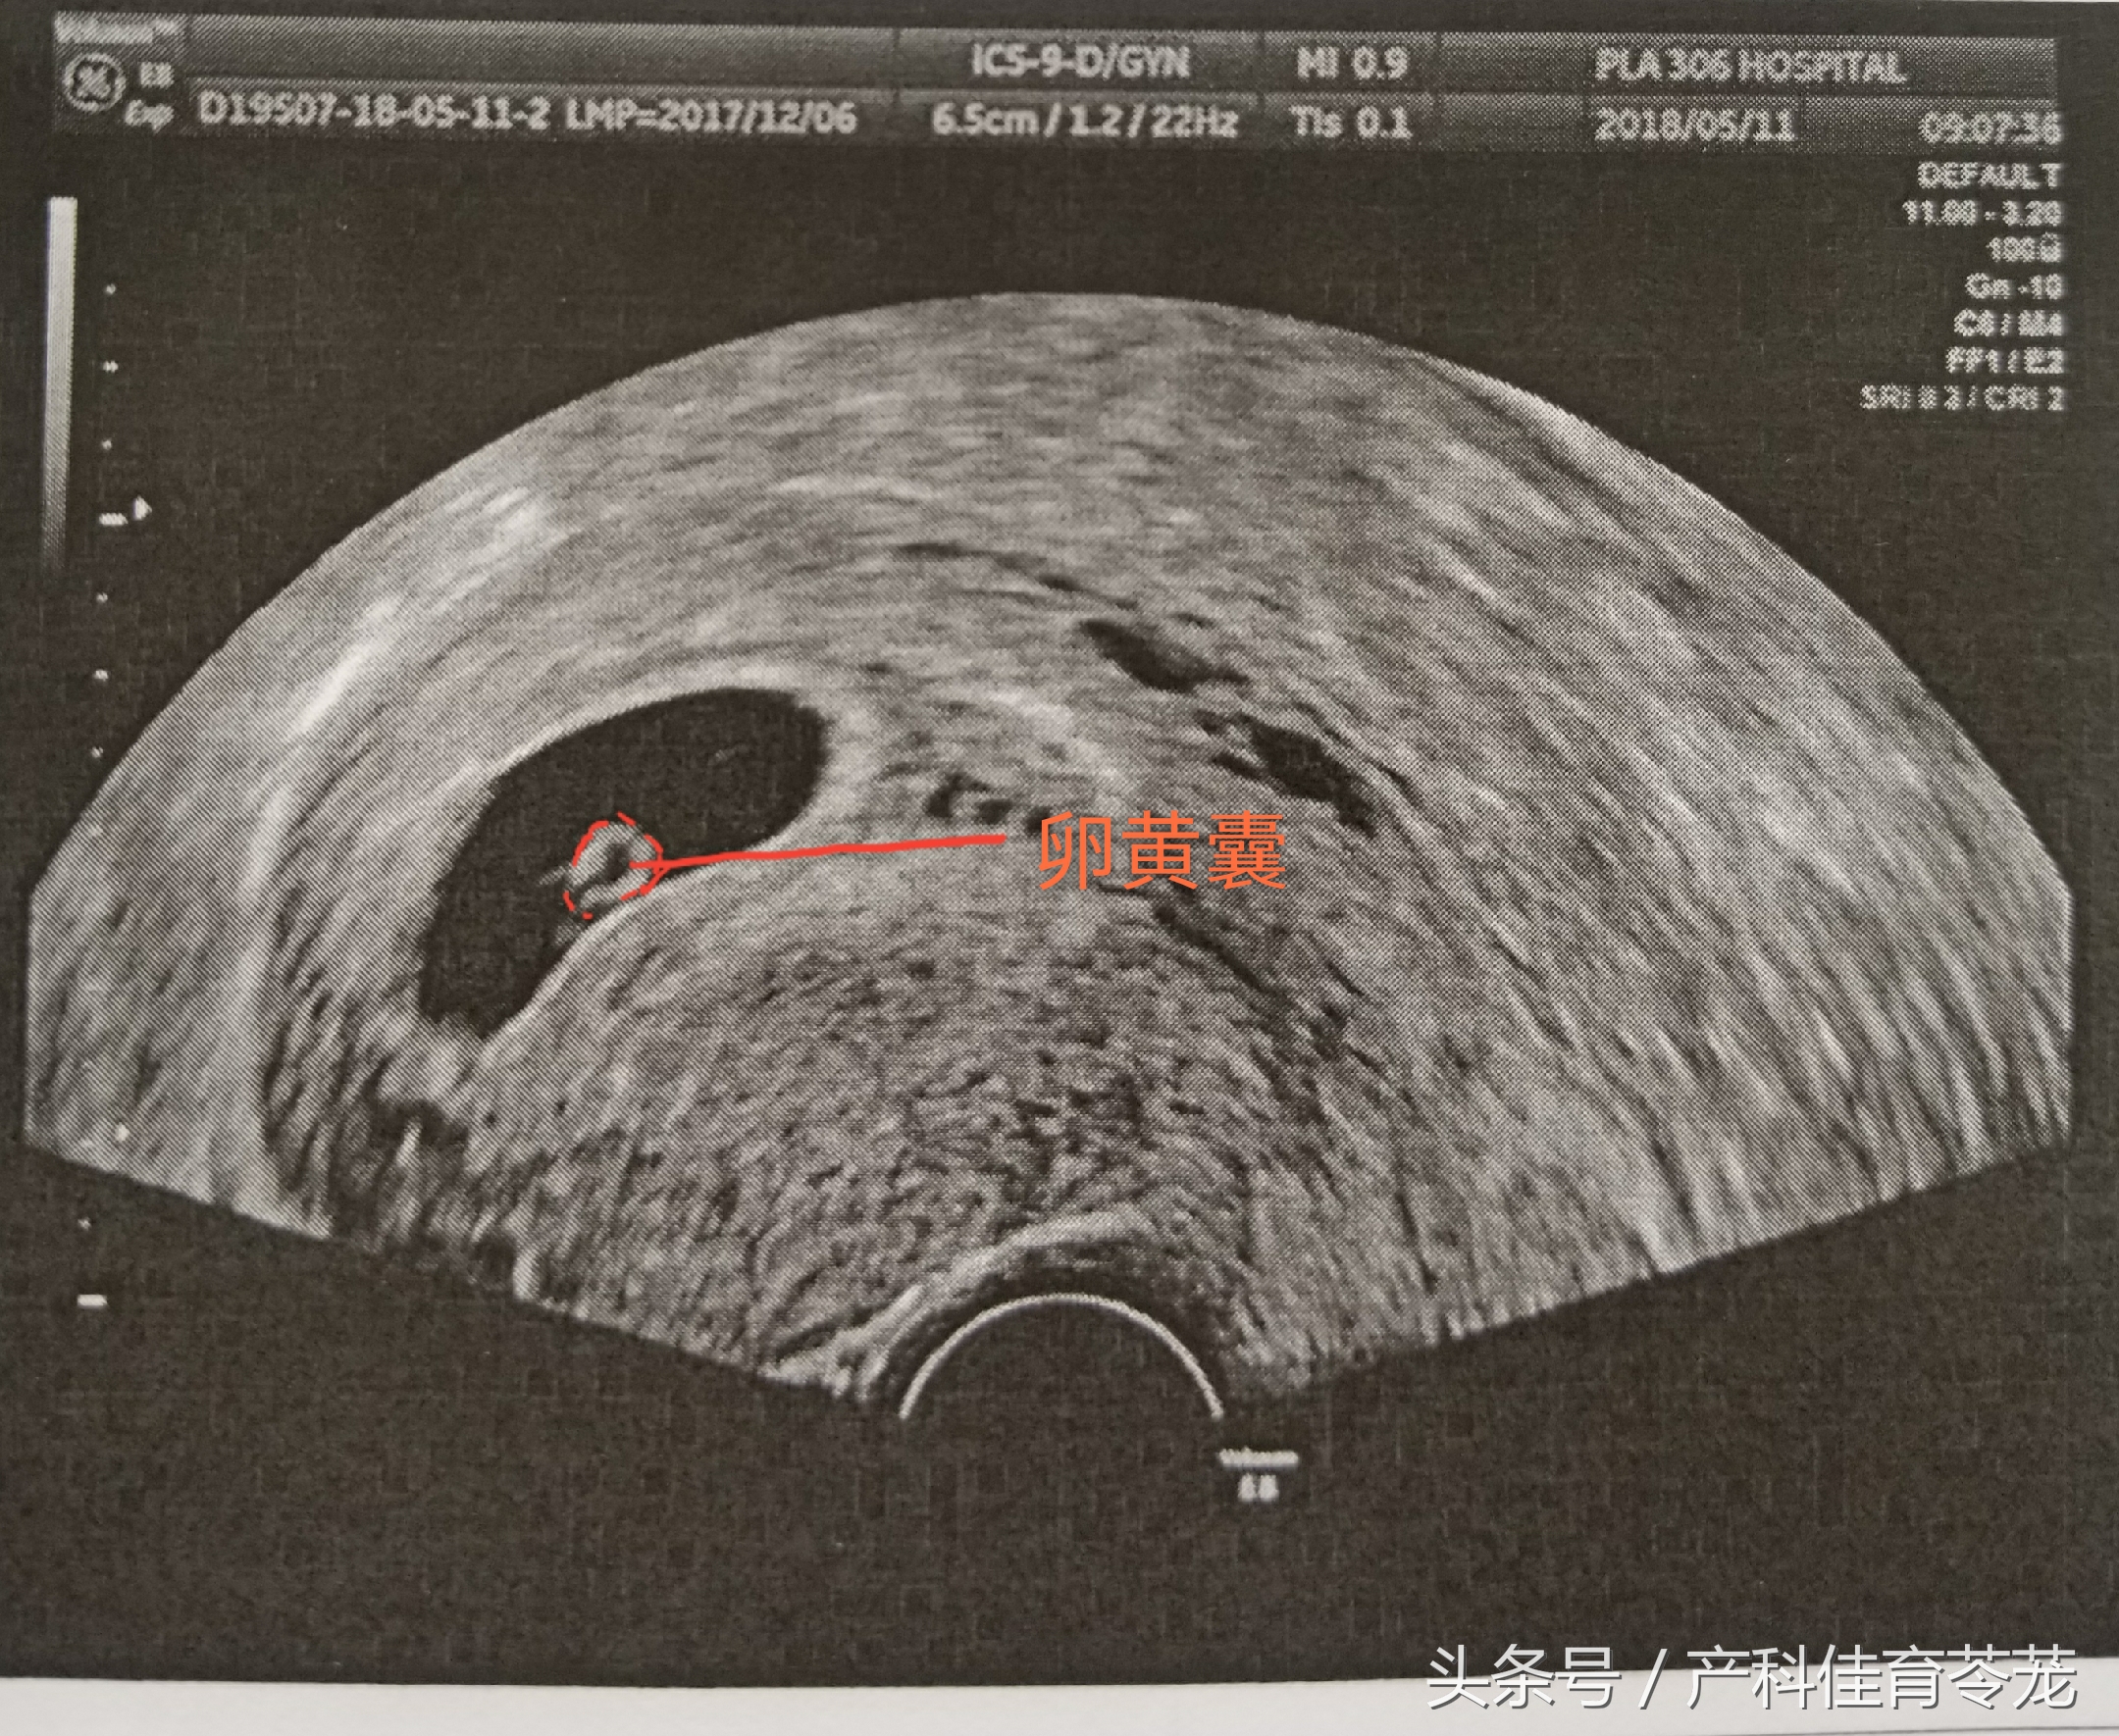

二、卵黄囊(Yolk Sac)

卵黄囊是附着在胚胎上的膜囊,是妊娠囊内超声能看到的第一个解剖结构。